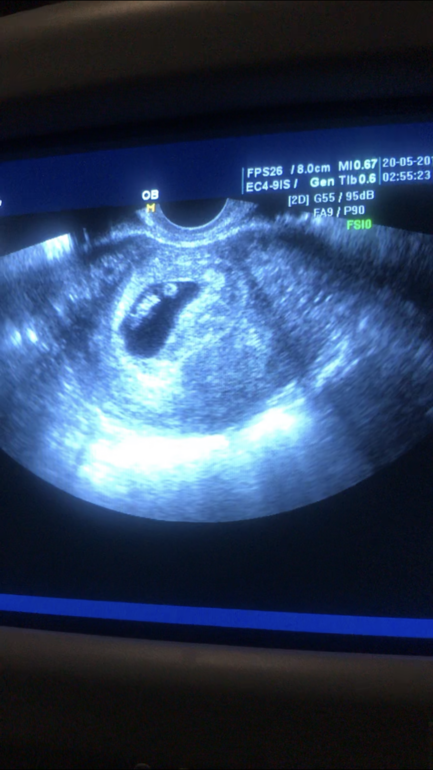

6 июня была наша первая встреча с акушеркой.

После последнего скана в репродуктивной клинике нам было сказано встать на учёт в «местной поликлинике». Позвонили, записались. Сказали, что сначала примет доктор, а потом Беременность будет вести midwife - акушерка. Запись аж через неделю. На всю поликл...